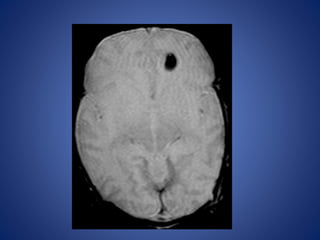

14 yr male with headache and seizures.

7 days old male child, with history of focal seizures.

DWI ADC

FFE

11 day old male child, with history of 1 episode of seizure.